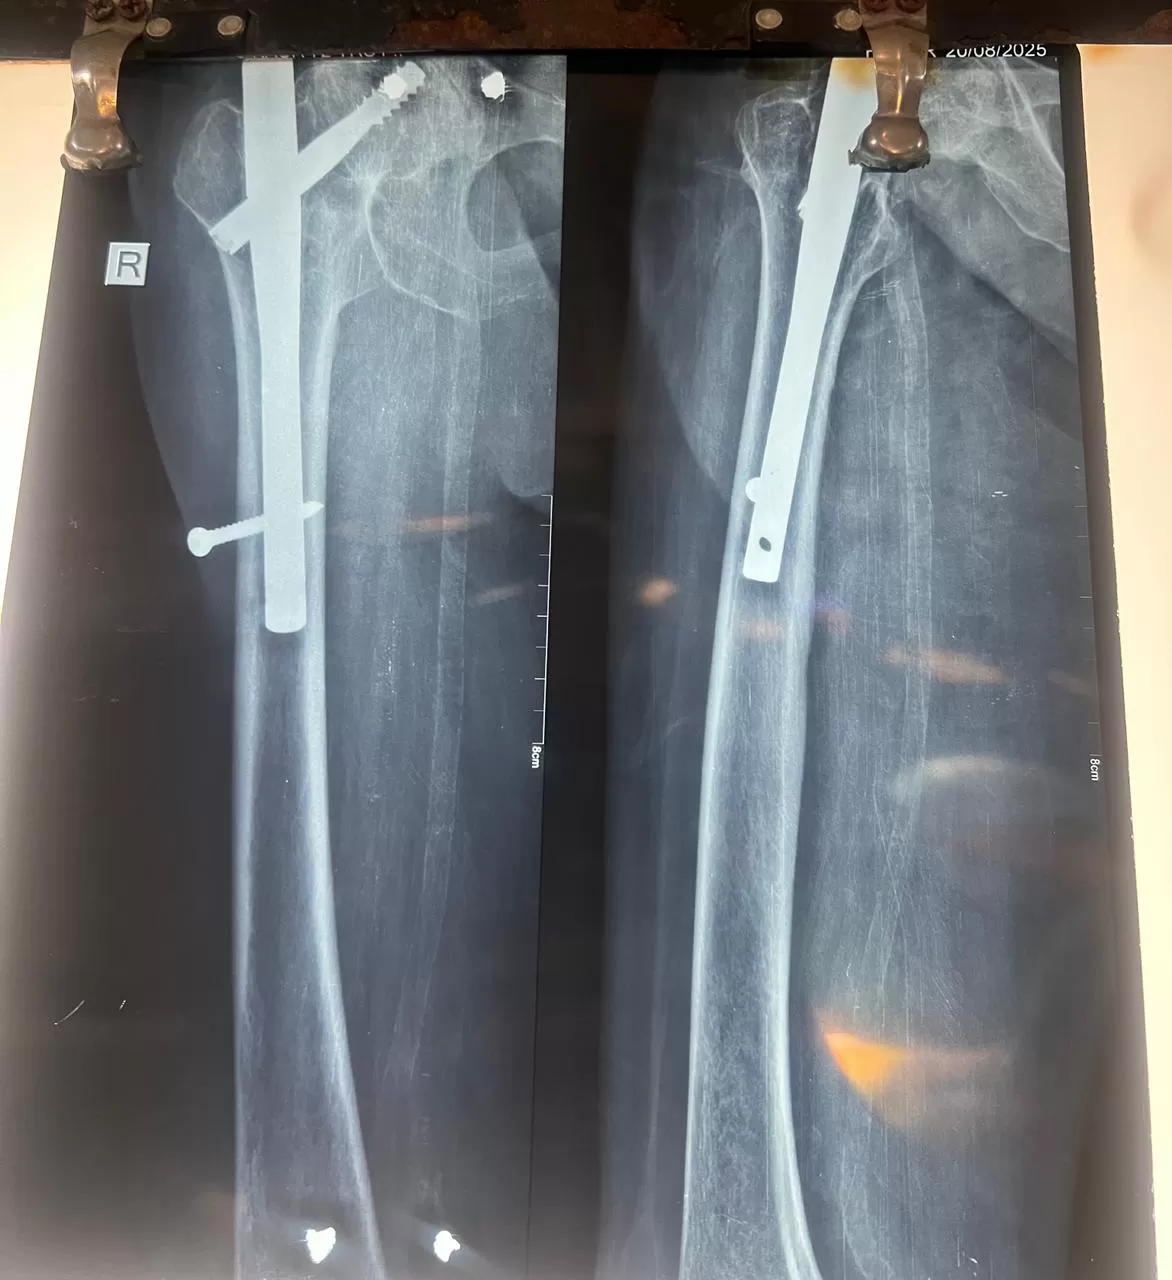

Name: Harbhajan

Date of Operation: 22 October

Age: 70 Years